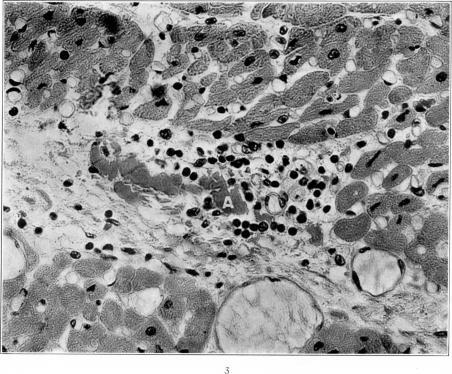

Studies on the Myocardial Aschoff Body: I. Descriptive Classification of Lesions.

Am J Pathol. 1934 Jul;10(4):467-488.15.

Studies on the Myocardial Aschoff Body: I. Descriptive Classification of Lesions.心肌阿绍夫小体的研究:I. 病变的描述性分类